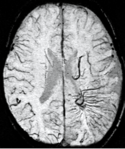

Multiple sclerosis (MS) is usually studied with FLAIR and contrast enhanced T1 imaging. SWI adds to this by revealing the venous connectivity in some lesions and presents evidence of iron in some lesions. This key new information may help understand the physiology of MS.[3]

The magnetic reasonance frequency measured with an SWI scan was shown to be sensitive to MS lesion formation. The frequency increases months before a new lesion appears on a contrast enhanced scan. At the time of contrast enhancement the frequency increases rapidly and remains elevated for at least six months.[4][5]